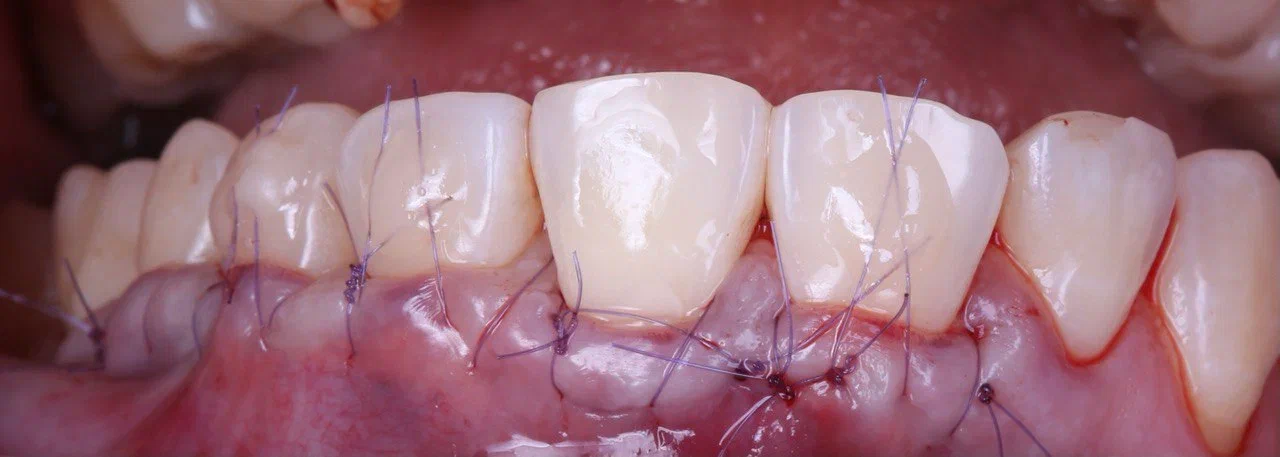

- отделённый участок «родной» десны вместе с подшитым трансплантатом подтягивается так, чтобы закрыть шейки проблемных зубов, и фиксируется швами.

Швы выглядят жутко, но будут сняты через 2 недели

Сама операция на этом заканчивается. Хотя процедура безболезненна, назвать её безобидной нельзя. После неё возникает отёк и гематома — не то, чтобы они сильно осложняют жизнь пациенту, но неприятные ощущения доставляют. Поэтому сразу после операции мы ему предлагаем специальное мороженое для охлаждения ротовой полости, а также прописываем анальгетики, антибиотики, противоотёчные таблетки или уколы.